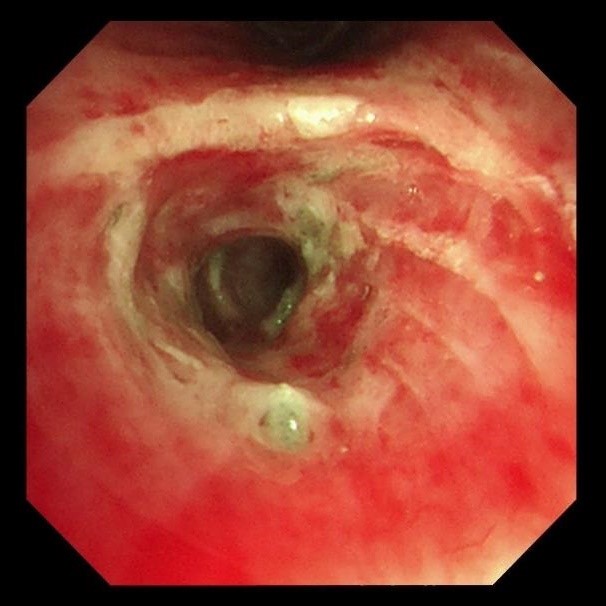

两天后复查支气管镜,发现患者左下叶背段远端细支气管仍有残留泥沙样异物。团队采用超细支气管镜联合冷冻技术,通过冷冻探头将异物凝固,再用超细活检钳逐支清理,实现对远端气道的彻底清理,实现气道“零死角”。

(远端支气管治疗后)